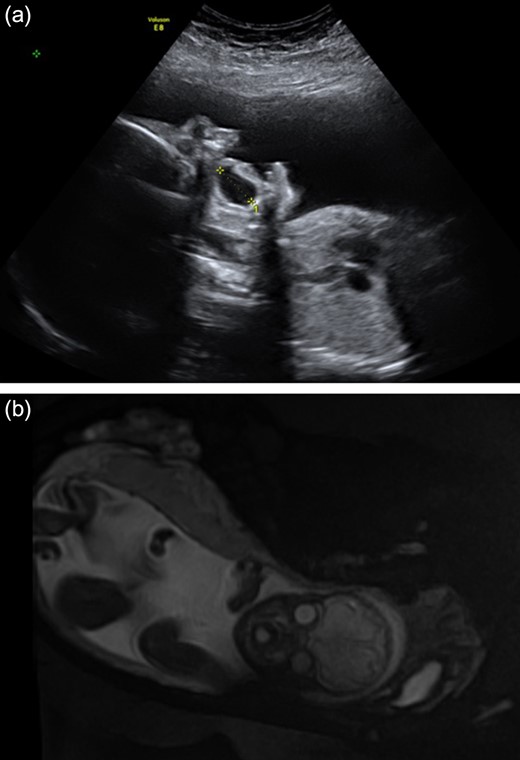

A foetus was noted on the 22-week scan to have a large intralingual mass posterior to the foetal lips. It was deemed to be fluid-filled and measuring 19.6 mm × 16.8 mm × 24 mm. The mother was therefore referred to a tertiary foetal medicine department to be reviewed. Serial ultrasound and MRI imaging showed that this defect grew in proportion to the foetus (Fig. 1a and b). In view of concerns of potential airway obstruction at birth, an elective caesarean section was performed at 39 weeks gestation, with paediatric and otolaryngology teams present. At delivery, a large anterior tongue filling the oral cavity was noted, and the neonate initially required oxygen to maintain saturations. The baby was admitted to Neonatal Intensive Care Unit for observation, and was initially started on nasogastric feeds while assessing the effect of the oral cyst on the neonate’s ability to feed. The baby improved, maintained its saturations on air and it was found that the cyst did not impair oral feeding. The baby was therefore discharged from hospital at age 2 days with planned paediatric otolaryngology follow-up.

(a) and (b) Antenatal ultrasound at 28 weeks and MRI scan at 31 weeks demonstrating large fluid-filled oral cyst.